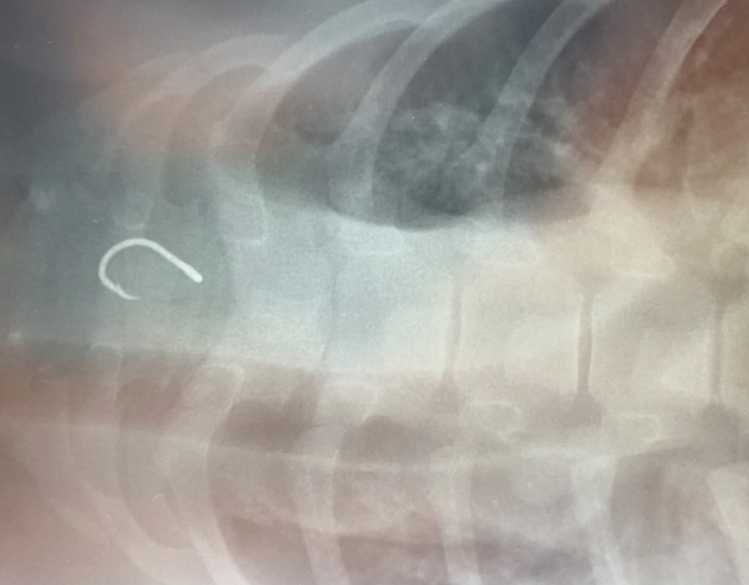

With entanglement and ingestion of ocean trash being a leading cause of death for endangered Hawaiian monk seals in the main Hawaiian Islands, quick diagnostic testing is crucial for the species’ survival. At Ke Kai Ola, our hospital on Hawai‘i Island, conservation technologies like our portable X-ray machine have proved critical in identifying hook ingestions, as well as other life-threatening ailments.

Our veterinary experts can bring the portable X-ray machine directly to the rescued seal’s pen to look inside its body, reducing the need to handle and transport the animal. The waterproof machine takes radiographs wirelessly and then transmits them digitally to a computer screen, providing us with immediate visual clues about an animal's health. If an ingested fishing hook or other gear is detected, our veterinarians can take the necessary steps to safely remove it and give the animal a second chance at life.